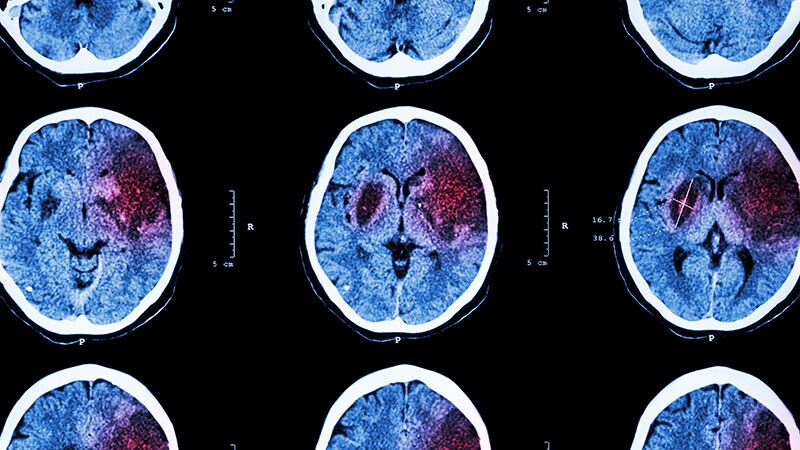

Taking ICH Cases Straight to Endovascular Center May Cause HarmRACECAT trial results suggest the longer travel times to the comprehensive stroke center -- rather than going to a closer

primary stroke center -- could be harmful for patients having a hemorrhagic stroke.